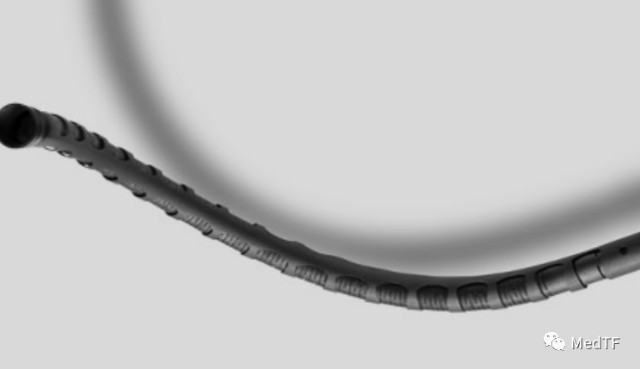

BENDIT微导管是一种新型的微导管,采用了独特蛇骨设计,这个设计允许其能通过各类狭窄段、弯曲的血管。能够用于诊断和治疗,并让术中通过远端和弯曲管道注入诊断和治疗试剂或者药物。

BENDIT微导管相比于传统的微导管拥有很明显的特点:

无限的3维操控

手柄可以360控制导管旋转,按照设想精度到达病灶部位。Bendit可以进入任何地方,包括各种类型弯曲的解剖结构。

超级弯曲性能

无论导管的长度,扭曲或环行如何,Bendit微导管都会在治疗结束时完美,准确地反映出外科医生执行的每个微小扭矩。由于从手柄到尖端的完全旋转反应可提供出色的体内扭矩。

定点定位锁止

在手柄设置有独特锁止系统,微导管一旦到达治疗部位就锁定保证微导管不会发生移动。这确保了将治疗快速准确地递送到需要的地方,而不必担心导管的移动将要求手术重新调整。

导航通道两不误

导航后,微导管的内腔被用作工作通道。可以在到达目标部位后立即开始治疗,从而节省了宝贵的时间。